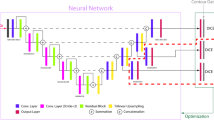

In this study, we propose an automated system for the segmentation of cancer brain metastases (CBM) using MRI images. The goal is the correlation with regards to the primary cancer site. The segmentation of CBM is a challenging task due to their wide range in terms of number, shape, size and location in the brain. We experimented with the training of a modified U-Net convolutional neural network (CNN) using N = 3474 brain image slices for training, Nv = 579 for validation and NT = 579 for testing from the public dataset BrainMetShare. The proposed model was evaluated on the testing data (NT), on a lesion-cross section basis with areas from 2.8 to 1225.7 mm2 and yielded a mean Sensitivity (SE) 0.70 ± 0.30, Specificity (SP) 0.77 ± 0.26 and Dice similarity coefficient (DSC) of 0.73 ± 0.29 across the entire dataset. The present results show the good agreement of the proposed method with the ground truth.